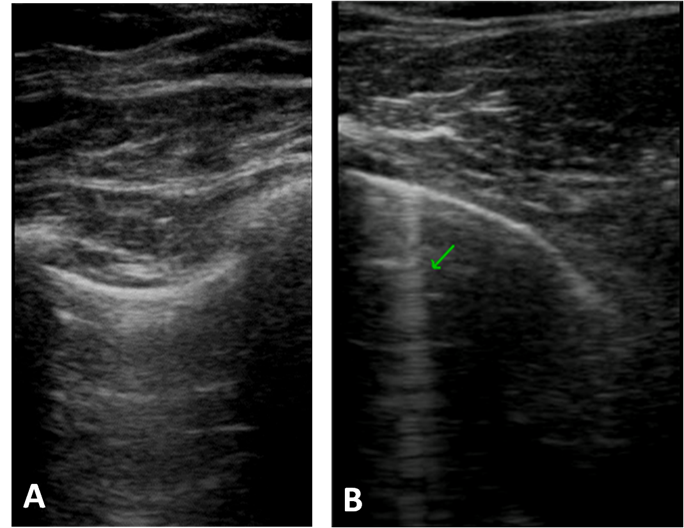

ILD rarely occurs in JDM, but it has a poor prognosis, with only 70% 5-year survival rate.26,27 Although it may be asymptomatic, it clinically presents with chronic and progressive cough and dyspnea. In adults, ILD is dermatomyositis most frequent pulmonary complication, affecting 30 to 50% patients, and anti-Jo-1 antibody positivity has a high predictive value for this serious outcome.22 In a case-control study with 59 JDM patients, 14% showed signs of ILD on chest HRCT and 26% evidenced a restrictive pattern on the pulmonary function test. It is reported that in these patients, asymptomatic lung disease can be diagnosed early through pulmonary function tests.5,26,27 Interestingly, a patient with JDM in our study had alterations in lung images (LUS and HRCT) and normal spirometry, being asymptomatic, anti-Jo-1 negative and with a 14 years chronic clinical course, with well-controlled clinical and laboratory activities at the time of the study (Figure 1). This patient was using mycophenolate mofetil and hydroxychloroquine, having already used glucocorticoids, azathioprine, cyclophosphamide and immunoglobulin. The duration of the disease may justify these initial pulmonary findings and indicates the importance of periodic pulmonary LUS screening, saving the patient from periodic radiation with the use of HRCT scans.

Figure 1 The score lung ultrasound evaluation in dermatomyositis patient with a total of B-lines to equal 8: (A) Left anterior axilar recess, without B-line and (B) Rigth posterior axilar recess, with B-lines (arrow).